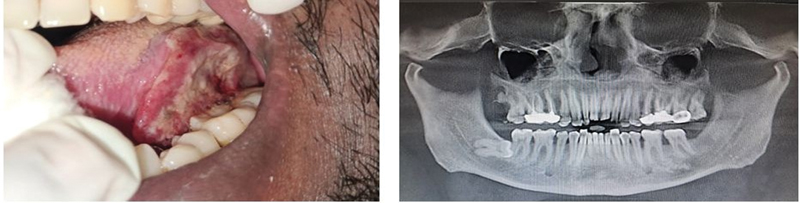

| Figure 2: Clinical and radiographic images of a 36-year-old female patient with cancer of the upper right alveolus with no known risk factors other than periodontitis.